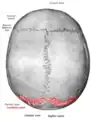

![]() Lambdoid suture (labeled at bottom right) | |

Parietal bones (above) and occipital bone (below).

Lambdoid suture seen from above.